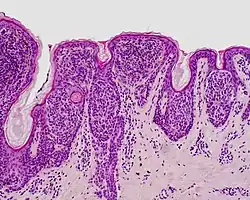

| Junctional nevus | Along the junction of the epidermis and the underlying dermis.[15] | May be colored and slightly raised.[16] |

|

ICD10: D22 ICDO: M8740/0 |